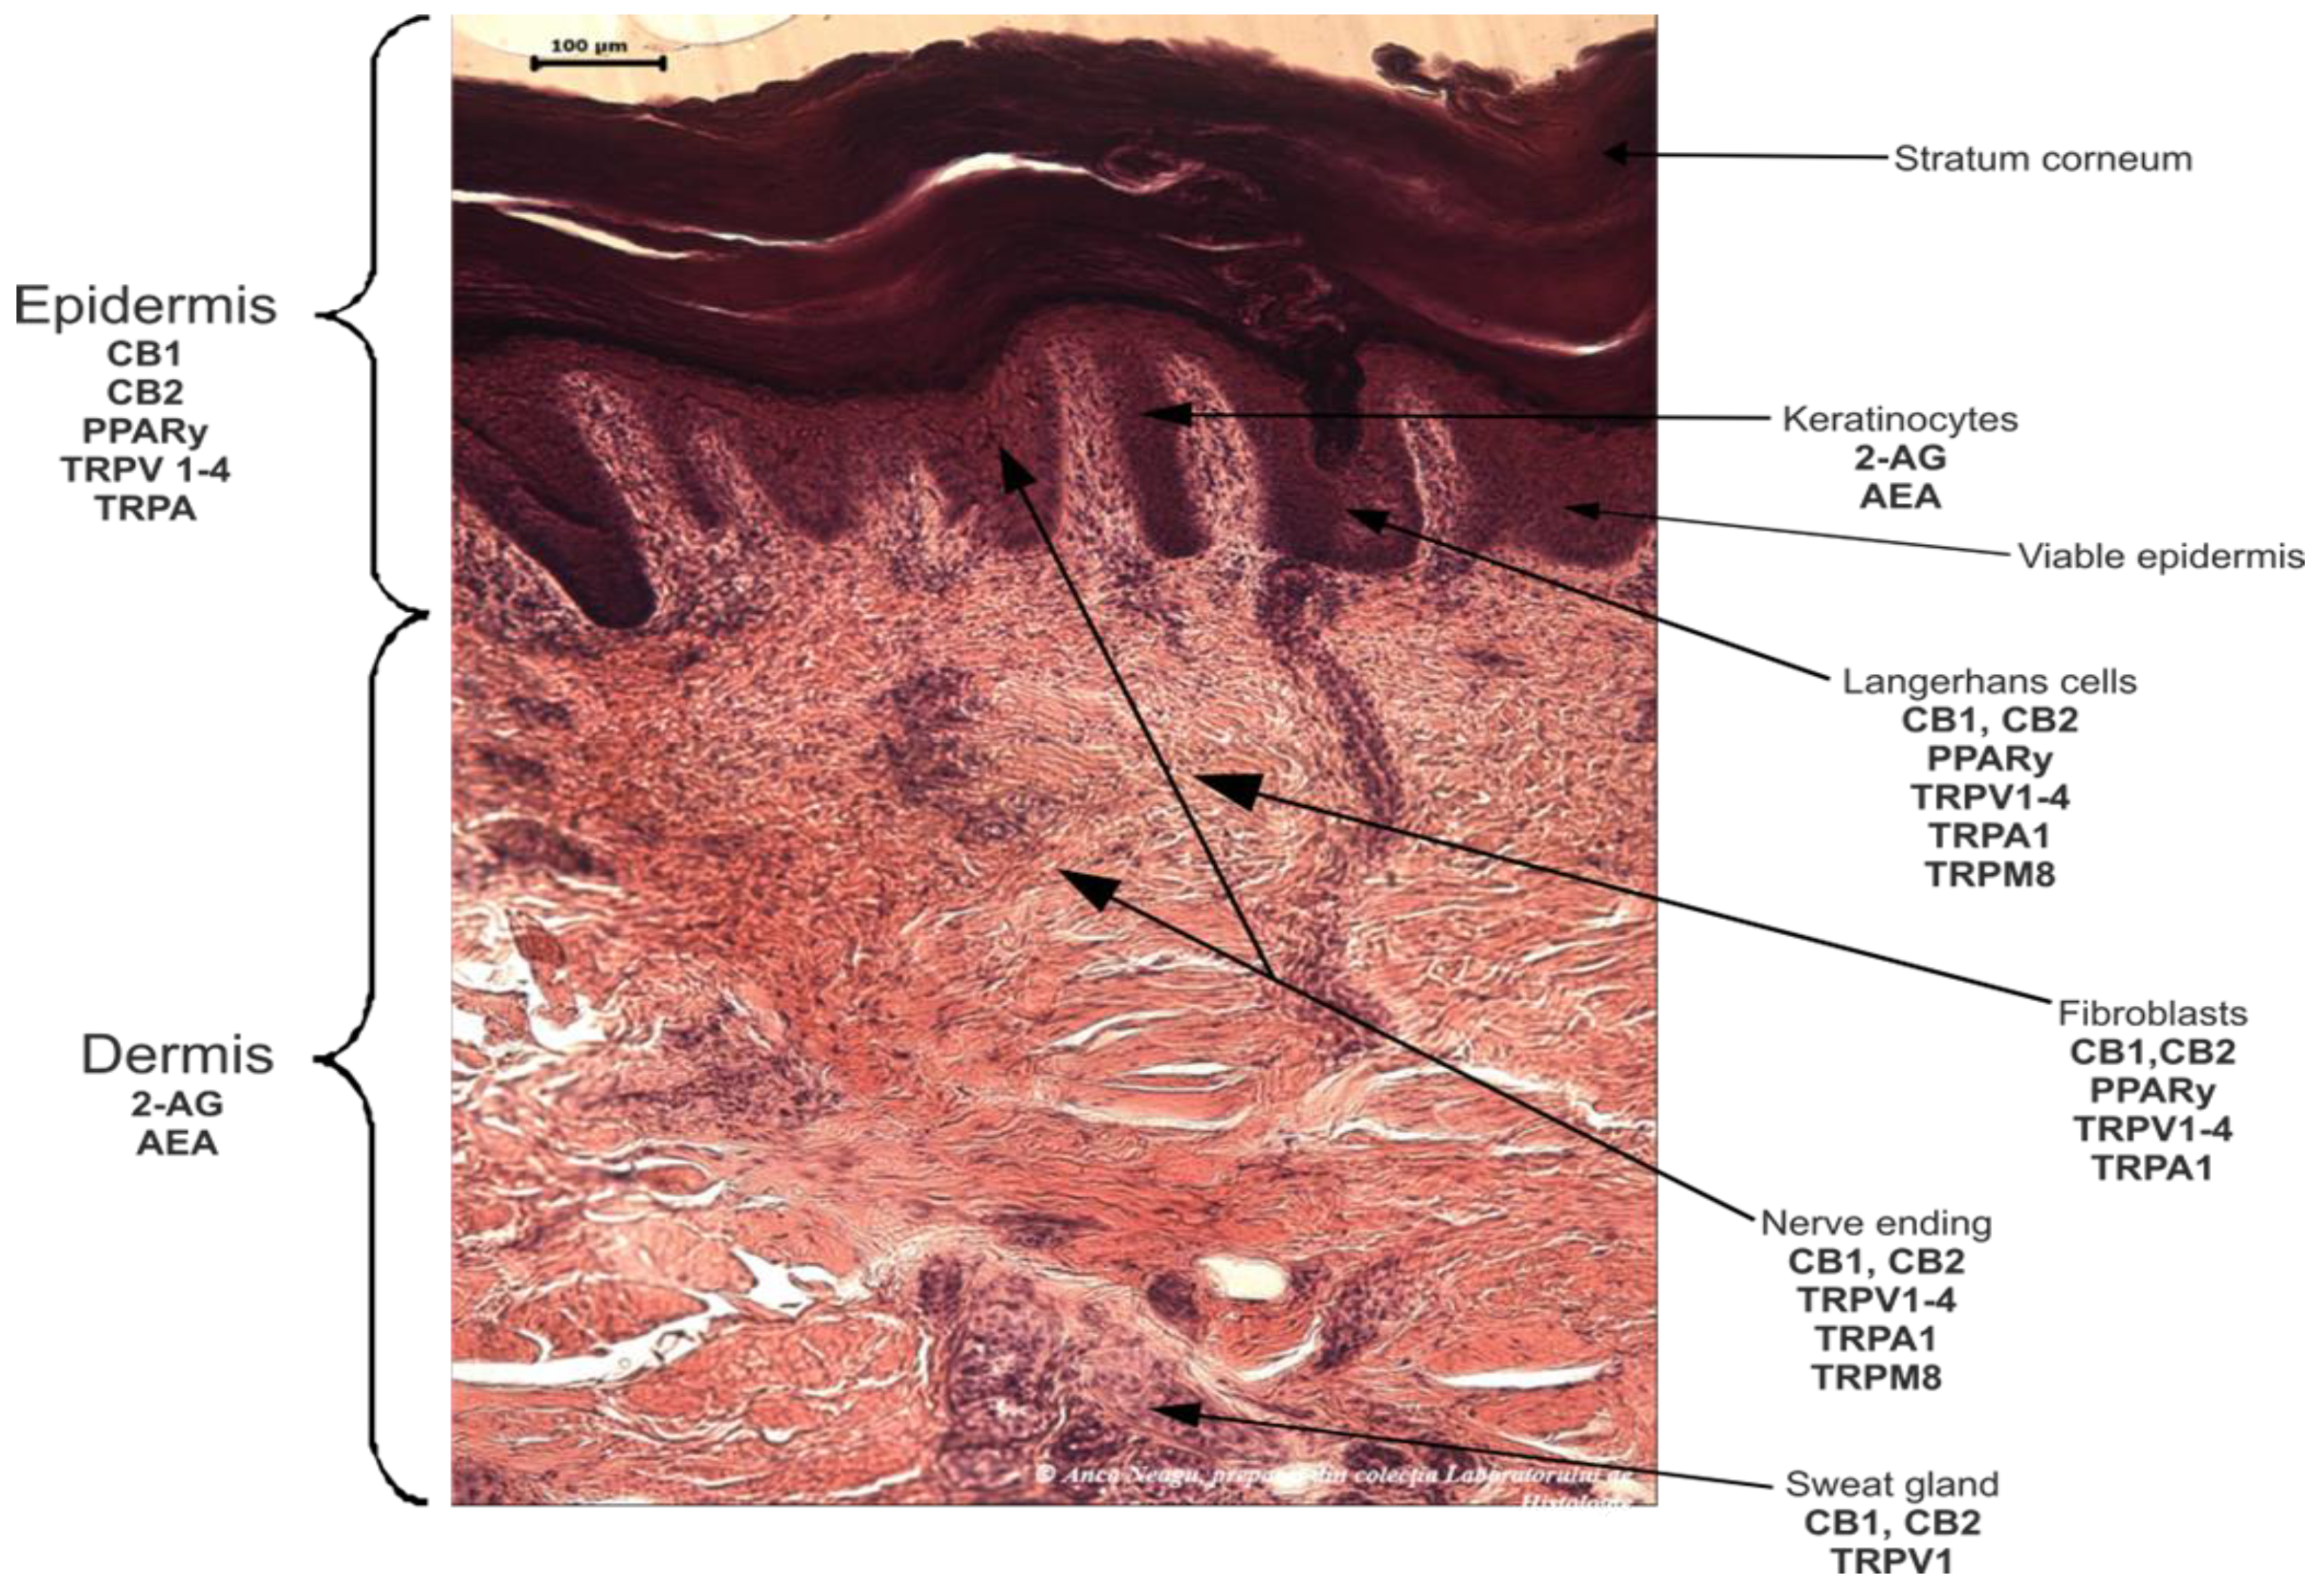

2.1.1. The Skin Endocannabinoid System

- del Río, C.; Millán, E.; García, V.; Appendino, G.; DeMesa, J.; Muñoz, E. The endocannabinoid system of the skin. A potential approach for the treatment of skin disorders. Biochem. Pharmacol. 2018, 157, 122–133. [Google Scholar] [CrossRef]

- Tóth, K.; Ádám, D.; Bíró, T.; Oláh, A. Cannabinoid Signaling in the Skin: Therapeutic Potential of the “C(ut)annabinoid” System. Molecules 2019, 24, 918. [Google Scholar] [CrossRef]

- Tüting, T.; Gaffal, E. Regulatory Role of Cannabinoids for Skin Barrier Functions and Cutaneous Inflammation. In Handbook of Cannabis and Related Pathologies; Elsevier: Amsterdam, The Netherlands, 2017; pp. 543–549. [Google Scholar]

- Kendall, A.C.; Pilkington, S.M.; Massey, K.A.; Sassano, G.; Rhodes, L.E.; Nicolaou, A. Distribution of Bioactive Lipid Mediators in Human Skin. J. Investig. Dermatol. 2015, 135, 1510–1520. [Google Scholar] [CrossRef]

- Maccarrone, M.; Di Rienzo, M.; Battista, N.; Gasperi, V.; Guerrieri, P.; Rossi, A.; Finazzi-Agrò, A. The Endocannabinoid System in Human Keratinocytes. J. Biol. Chem. 2003, 278, 33896–33903. [Google Scholar] [CrossRef] [PubMed]

- Ständer, S.; Schmelz, M.; Metze, D.; Luger, T.; Rukwied, R. Distribution of cannabinoid receptor 1 (CB1) and 2 (CB2) on sensory nerve fibers and adnexal structures in human skin. J. Dermatol. Sci. 2005, 38, 177–188. [Google Scholar] [CrossRef] [PubMed]